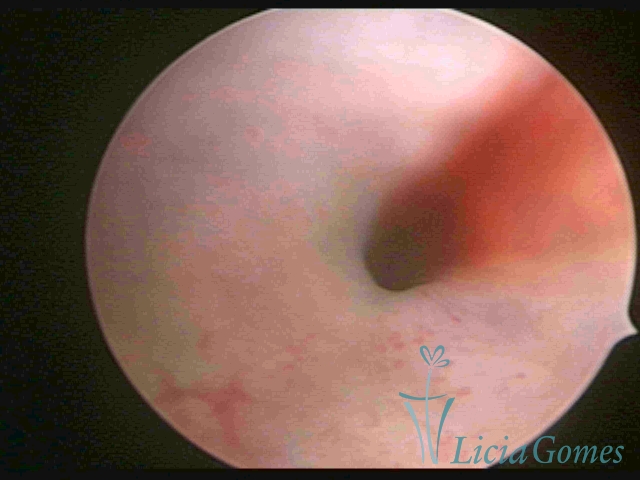

Segunda porção ou setor médio

No terço ou setor médio do canal cervical perdemos o detalhe das papilas, sendo possível a visualização de pregas e criptas. Normalmente observamos os sulcos longitudinais, que são os tecidos mais compactos, com a superfície mais vascularizada, cujos vasos seguem o seu trajeto.